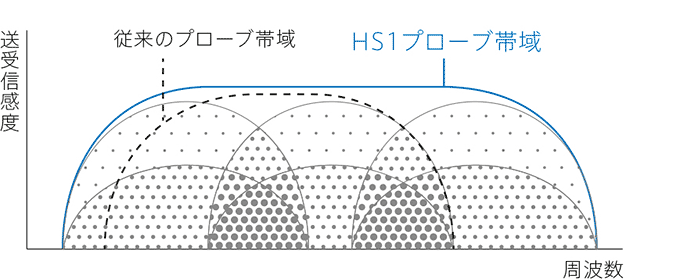

超広帯域プローブを最大限に活用するために、送受信技術の開発も必要でした。

そこで、コニカミノルタは、複数の周波数成分を合成送信するTriad-THI※技術を実用化しました。

これは、プローブ帯域内に含む全ての差音・和音成分を使ったイメージング技術であり、従来のTHIよりも、分解能とペネトレーションを高度に両立することを可能にしました。

高周波帯超広帯域プローブとこの帯域を最大限利用するためのTriad Tissue Harmonic Imaging技術。

それにより、表層・浅部を含めた関心領域全域の高画質化を実現したSONIMAGE HS1。